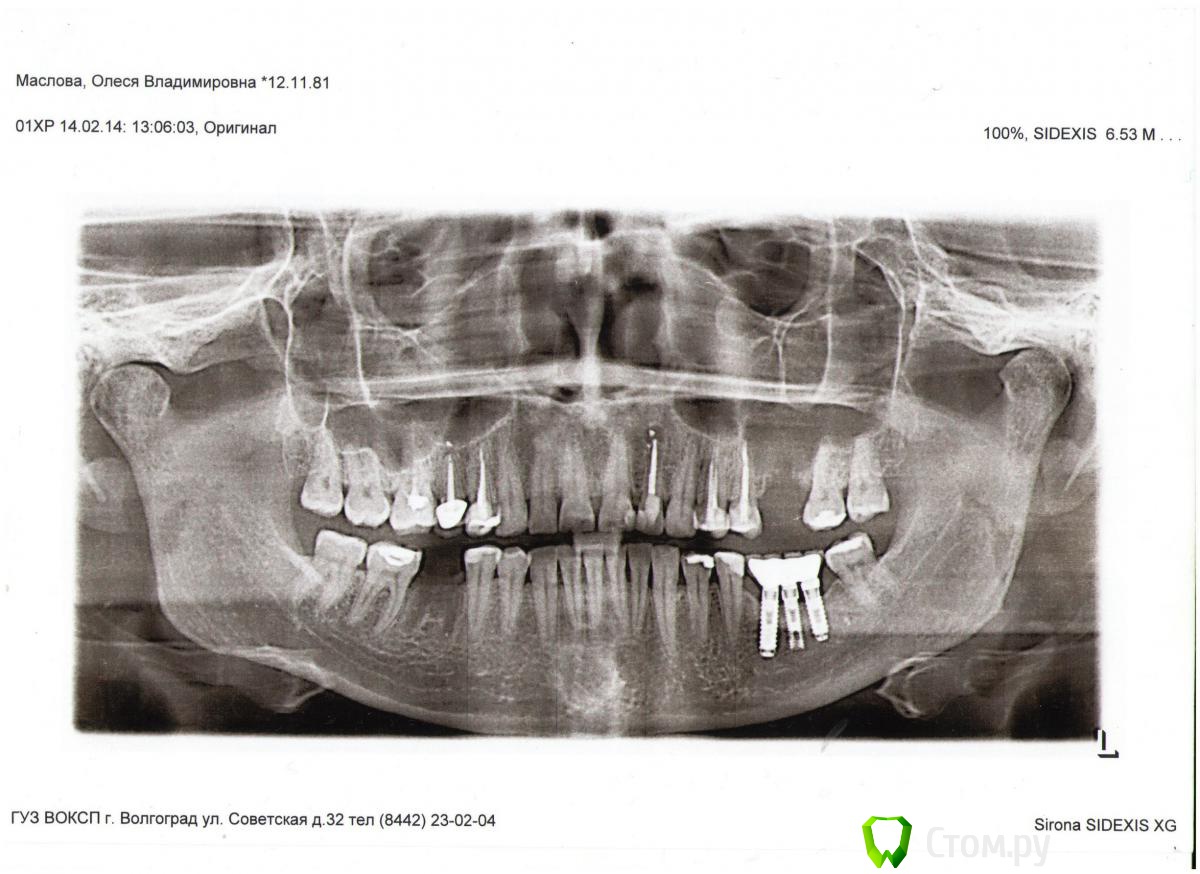

olesya.1211 Опубликовано 5 апреля, 2014 Автор Поделиться Опубликовано 5 апреля, 2014 А Вы какой зуб имеете ввиду? 22й ?Как давно его лечили(перелечивали)? А Вы какой зуб имеете ввиду? 22й ?Как давно его лечили(перелечивали)?22 й зуб. Кисту в нем я лечили в 2006 году методом депофореза, лечение прошло успешно, костная ткань наросла и на снимке все было отлично. Пол года назад (снимок 1) тоже вроде было без изменений. А в прошлом месяце я сделала ортопонограмму (снимок 2), делала его для консультации хирурга по поводу предстоящей имплантации, и хирург заметил, что над 22м зубом есть затемнение, сказал, что киста дала рецидив и лечить необходимо хирургически (резекция верхушки корня). В другой клинике предложили пролечить терапевтически с применением лазера. Вот я и не знаю каким методом лучше перелечить кисту. Подскажите, пожалуйста, какой метод лечения будет более надежный? Ссылка на комментарий

olesya.1211 Опубликовано 7 апреля, 2014 Автор Поделиться Опубликовано 7 апреля, 2014 К сожалению, снимка до лечения у меня нет. Знаю, что изначально, киста образовалась из-за неправильного лечения, так как пролечив зуб, спустя какое-то время он внезапно разболелся, тогда врач на снимке и обнаружила кисту, помню, что сказала, что киста довольно таки большая и предложила лечение депофорезом, но без гарантии. Сейчас по сравнению с прошлым годом (снимок 1) киста увеличилась (снимок 2), пока не болит. Ссылка на комментарий

olesya.1211 Опубликовано 24 апреля, 2014 Автор Поделиться Опубликовано 24 апреля, 2014 Просто найдите стоматолога-эндодонтиста для которого это рутинаСкажите, пожалуйста, а размер кисты (снимок 2) не слишком большой для терапевтического лечения? Я читала, что при больших кистах только резекция. И зуб мертвый, хрупкий, нужно ли его после лечения коронкой покрывать? Ссылка на комментарий

Гарриевич Опубликовано 24 апреля, 2014 Поделиться Опубликовано 24 апреля, 2014 Скажите, пожалуйста, а размер кисты (снимок 2) не слишком большой для терапевтического лечения? Я читала, что при больших кистах только резекция. И зуб мертвый, хрупкий, нужно ли его после лечения коронкой покрывать?То, что Вы называете кистой, в реальности кистой может не являться. Так что размер не имеет значение. Если канал Вам пломбировали именно метапексом с гуттаперчей (Вы не путаете?), то нужно перепломбировывать + необходима герметичная реставрация, после чего наблюдение через полгода-год и если не будет положительного результата - резекция верхушки корня. Ссылка на комментарий